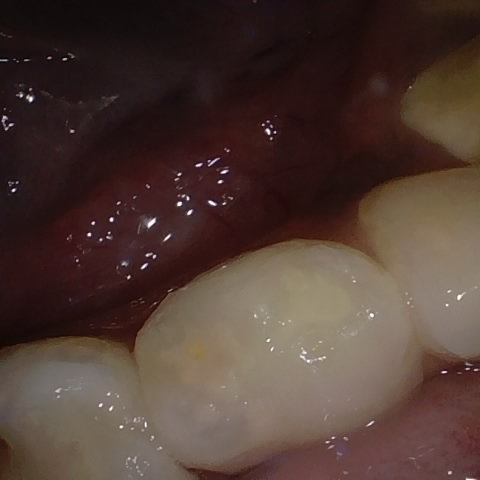

Annotated as "Good"